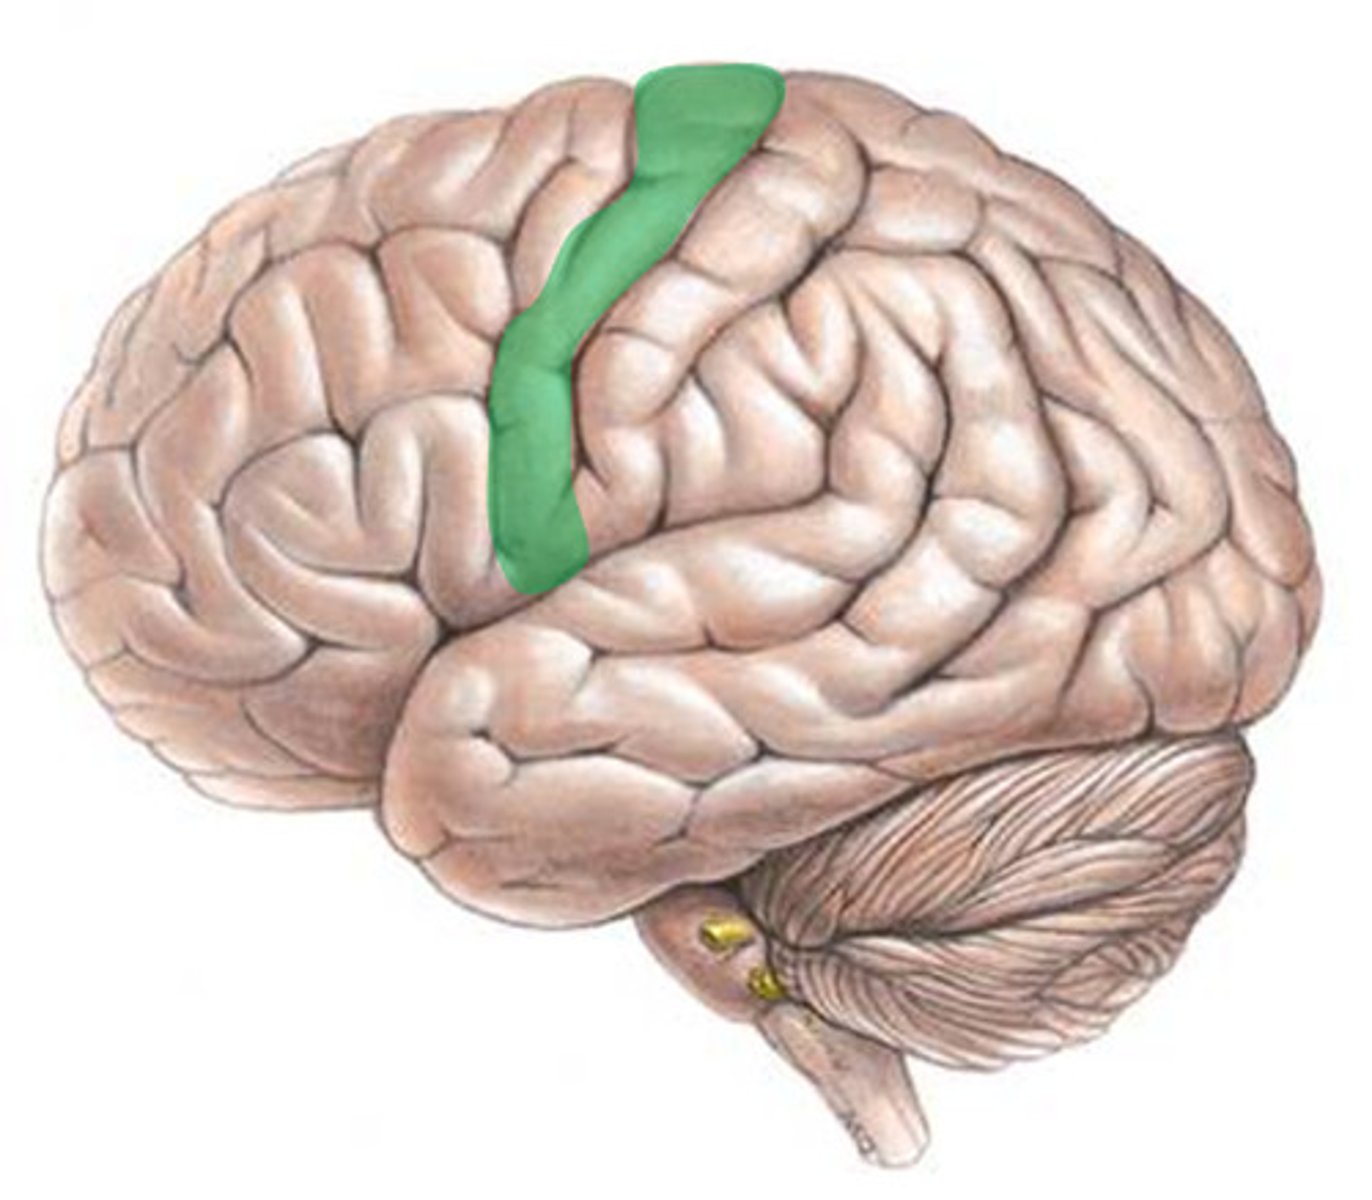

Cerebrum: Sulci and Gyri

Central Sulcus,

Precentral gyrus,

Postcentral gyrus

Central Sulcus

Precentral Gyrus

Postcentral Gyrus